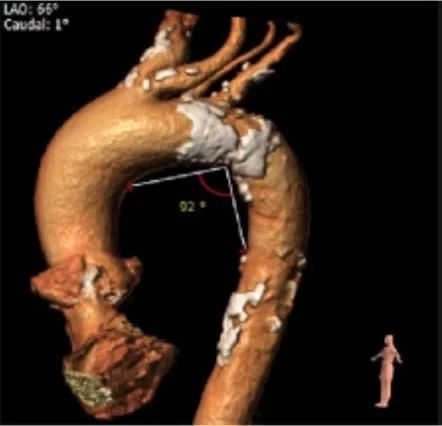

外周血管及主动脉弓解剖:

入路血管扭曲,双侧血管内径良好,所见主动脉血管壁显著钙化。

患者入路血管轻度扭曲,双侧血管内径良好,腹主动脉下段瘤样扩张。术中选择右股动脉为主入路,左侧位辅入路,手术过程要谨慎、轻柔,避免入路血管及腹主动脉瘤并发症。